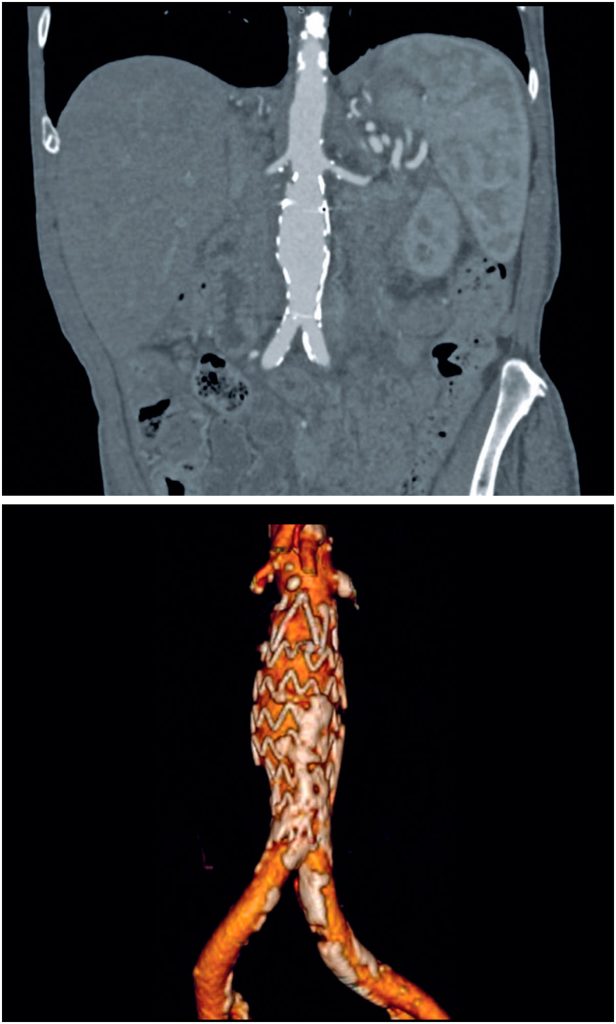

Spontaneous non-aneurysmal aortic rupture is rare and is usually attributed to penetrating aortic ulcers, infections, tumor infiltrations, or inflammatory and collagen diseases. Chronic rupture is infrequent but extremely rare in non-aneurysmal aortas, which makes diagnosis difficult because the absence of an aneurysm can mislead the physician to rule out rupture. Here, we describe the case of an 85-year-old male, who was undergoing oncological investigation for weight loss, inappetence, and back pain. Computed tomography and magnetic resonance imaging performed 3 months before admission showed a contained pseudoaneurysm of the infrarenal aorta associated with significant aortoiliac calcification and images suggestive of peritoneal implants. The patient was referred to our oncological center and underwent abdominal computed tomography for oncological investigation and staging. The patient was urgently admitted to the intensive care unit after a critical finding of contained rupture of the infrarenal aorta during the scan. Endovascular repair was indicated, and the patient was successfully treated with implantation of an Endurant IIs 25 × 25 × 70 mm endoprosthesis. No procedural complications were observed. Postoperative course was uneventful, and the patient was discharged on the fifth postoperative day. Control computed tomography performed 1 and 6 months after surgery showed no leaks. This case emphasizes the importance of communication between the radiologists and attending physicians. As the rupture was punctual and well defined in the computed tomography and angiography images, endovascular repair with an aortic cuff was safely performed, and the procedure time was reduced.